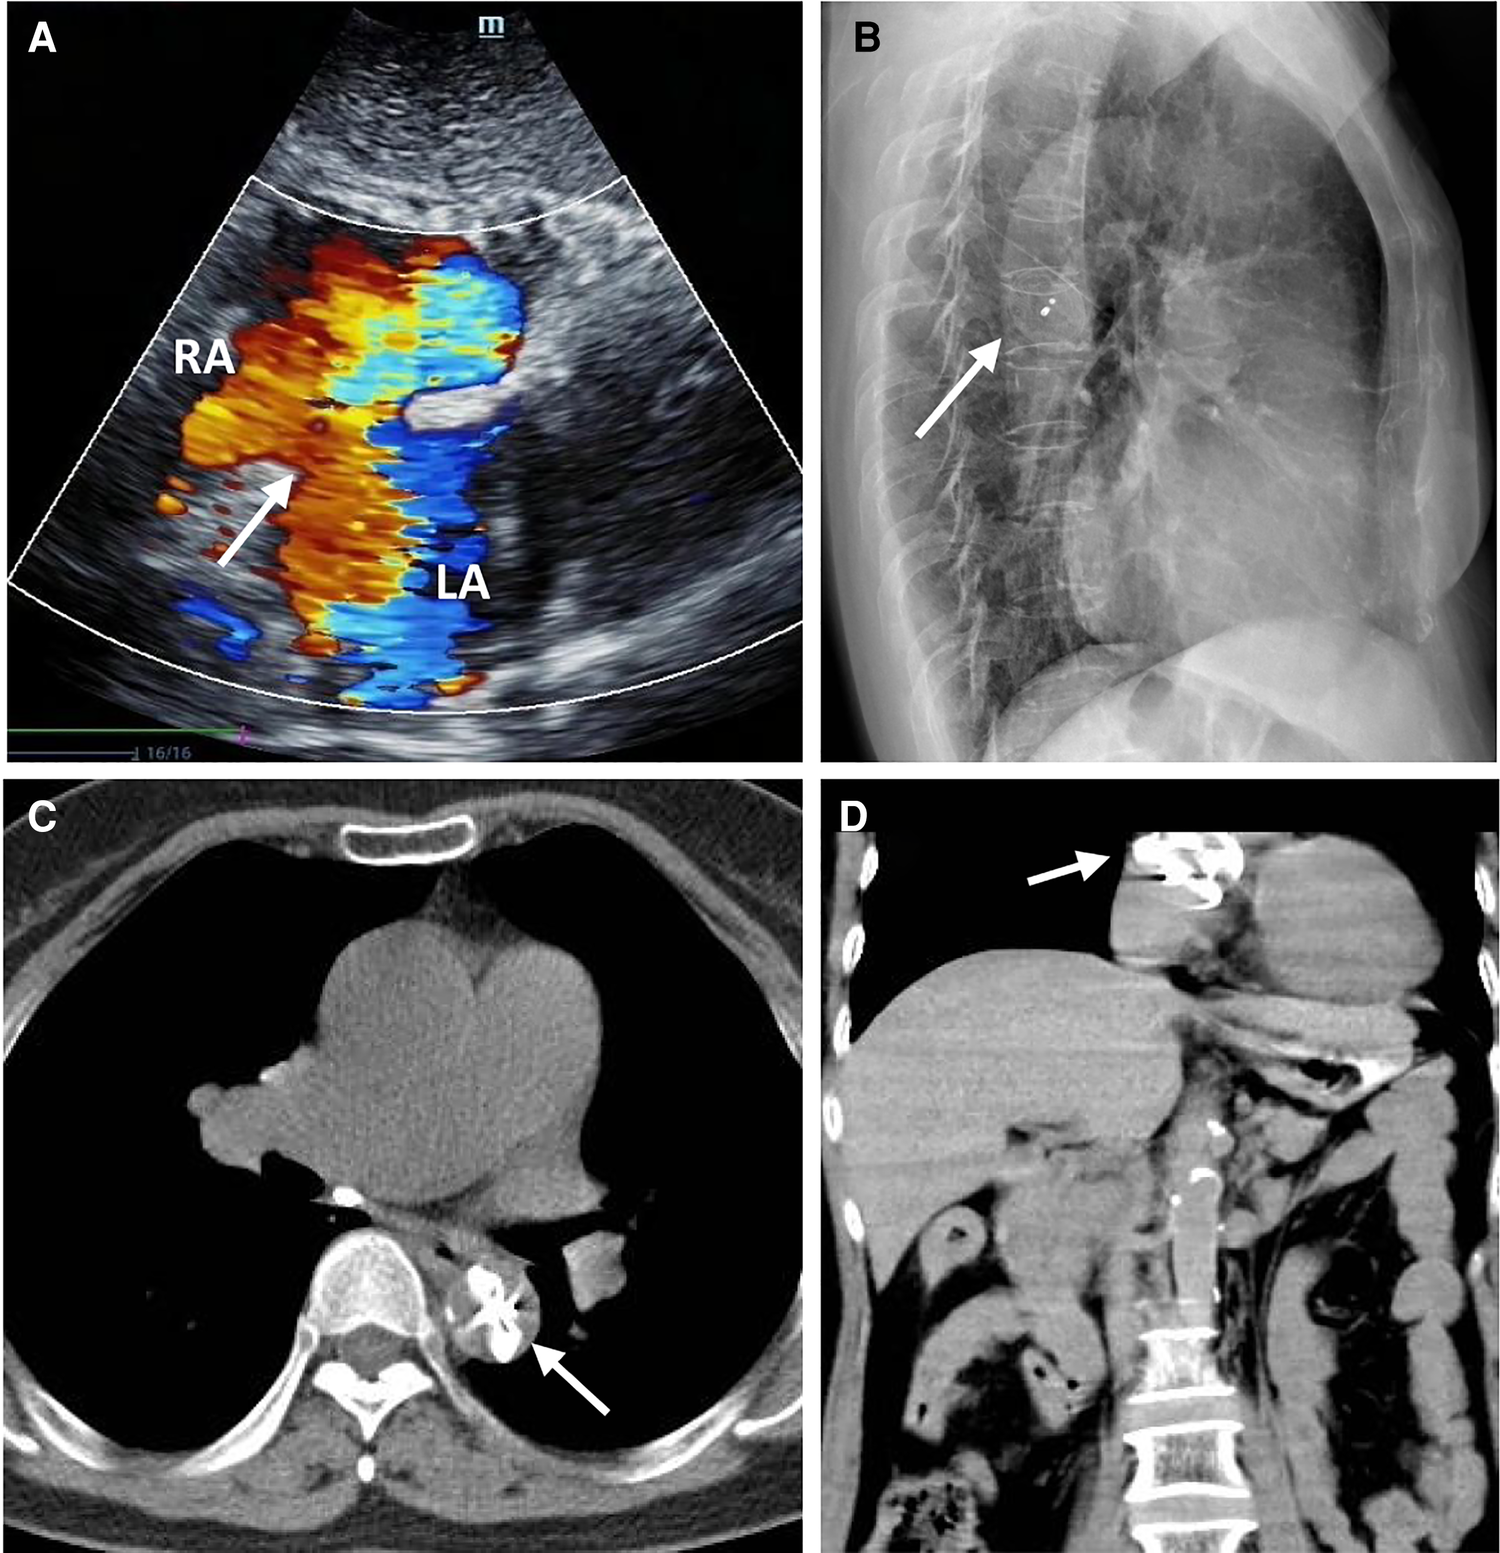

Figure 2

The ASO device embolization. Transthoracic echocardiography showing no occluder device and an interrupted echo (white arrow) in the middle of the atrial septum associated with a large number of left to right shunt flow (A); The lateral chest x-ray showed that the embolized occluder was located in the descending aorta (white arrow) (B); The chest CT showed that the embolized occluder device (white arrow) was located at the descending thoracic aortic isthmus (transverse view, C), (coronal view, D).